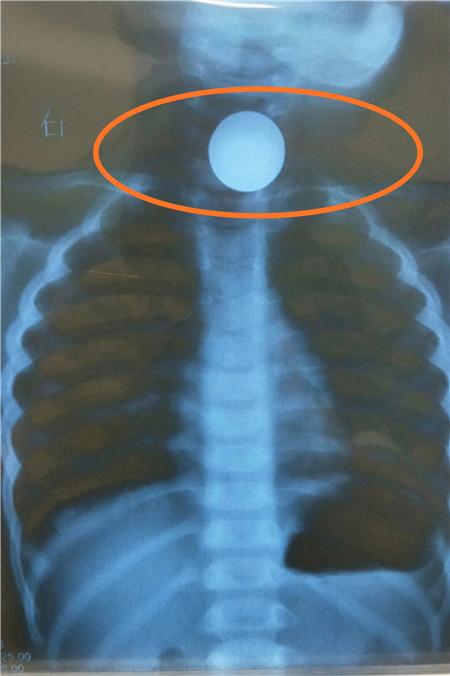

CT清晰可见食道有异物。

在社区医院,医生给星星拍了CT之后,发现有疑似硬币的异物卡在星星的食道口。此时,陈女士回忆起事发前她看到星星在玩一枚硬币,结合这一细节,医生判断,这个异物有极大可能就是硬币。由于社区医院条件有限,社区医院医生建议陈女士转院到就近的成都医学院第一附属医院。